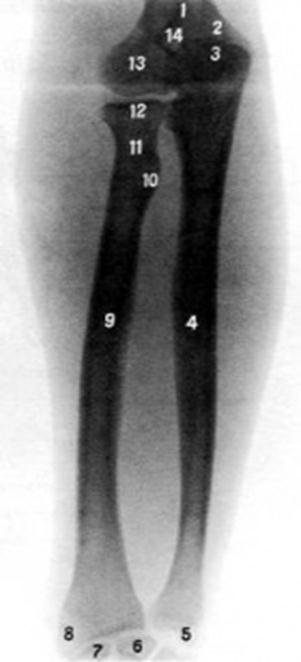

S: Цифра 9 указывает на …

S: Цифра 4 указывает на …

S: На рентгеновском снимке изображен articulatio ### (латинский язык).

S: Стрелка указывает на lig....

S: Стрелка указывает на lig....

S: Стрелка указывает на lig....

S: Стрелка указывает на...

S: Стрелка указывает на...

S: Стрелка указывает на articulatio...

S: Стрелка указывает на...

S: Стрелка указывает на ### сустав (русский язык).

S: Стрелка указывает на ### сустав (русский язык).